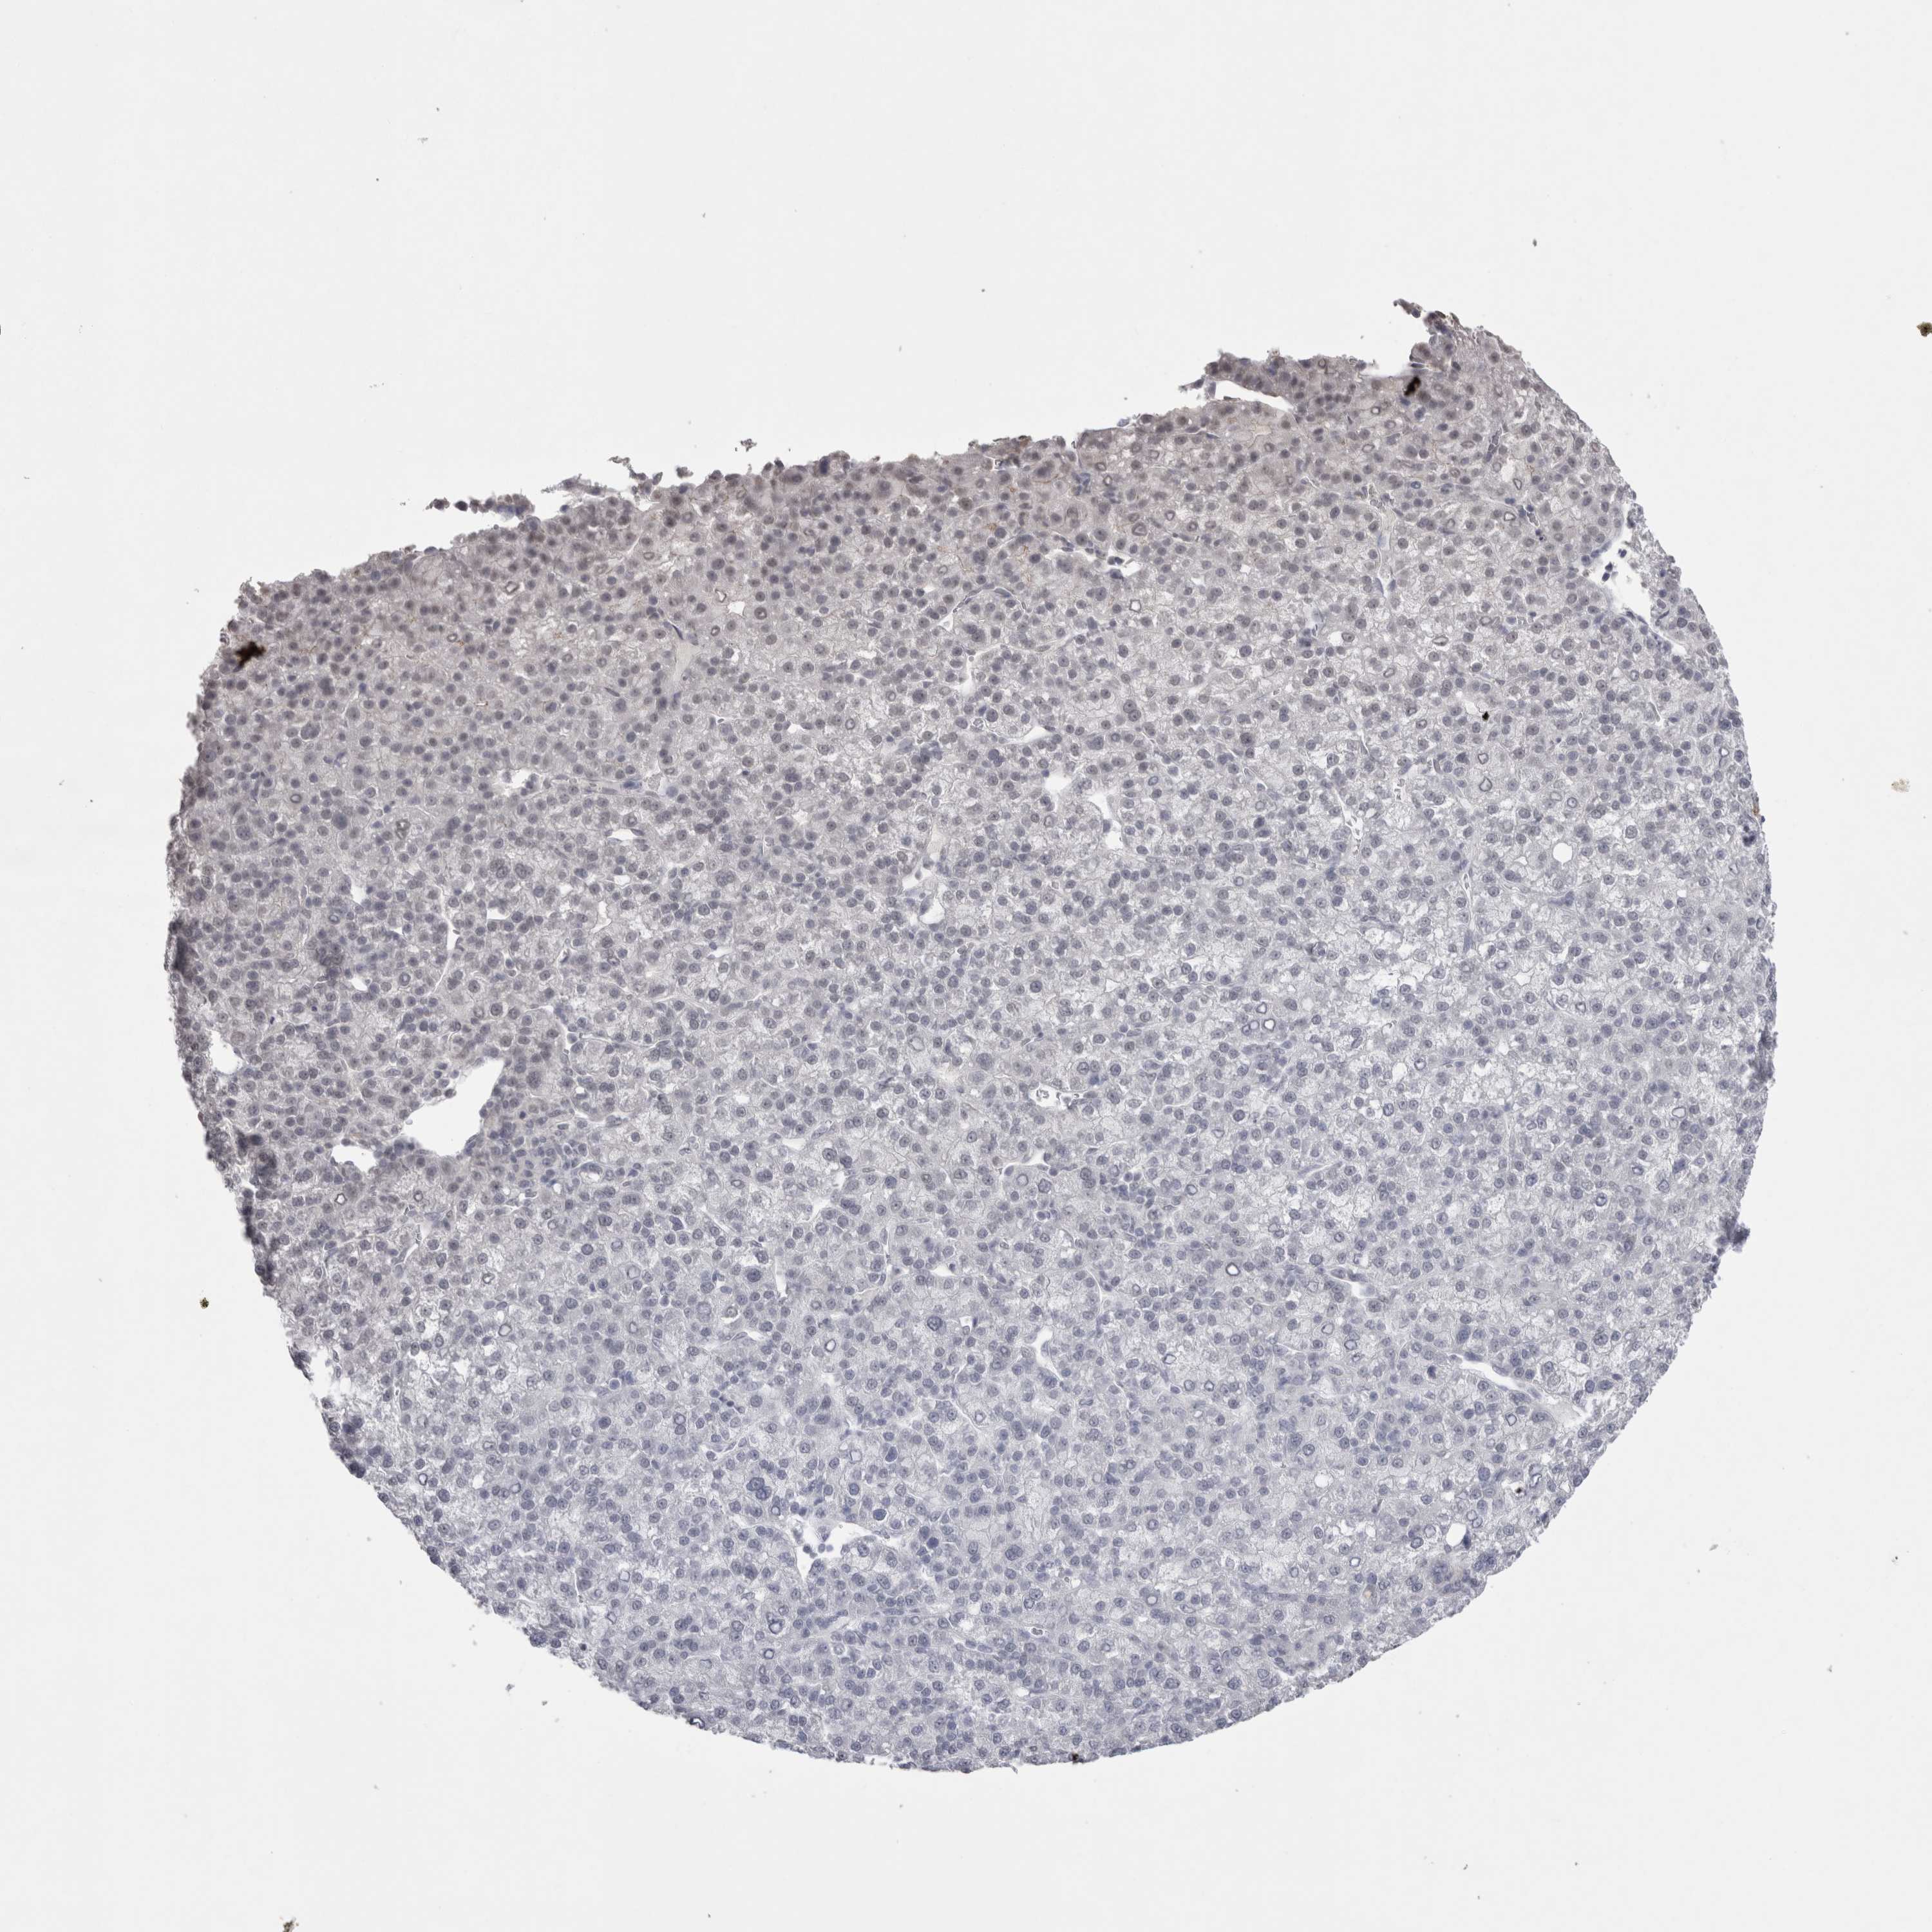

LIVER CANCER - Protein expressioni

A mouse-over function shows sample information and annotation data. Click on an image to view it in a full screen mode. Samples can be filtered based on level of antibody staining by selecting one or several of the following categories: high, medium, low and not detected. The assay and annotation is described here.

Note that samples used for immunohistochemistry by the Human Protein Atlas do not correspond to samples in the TCGA dataset.

Antibody stainingi

Antibody staining in the annotated cell types in the current human tissue is reported as not detected, low, medium, or high, based on conventional immunohistochemistry profiling in selected tissues. This score is based on the combination of the staining intensity and fraction of stained cells.

Each image is clickable and will lead to virtual microscopy that enables deeper exploration of all samples and also displays staining intensity scores, fraction scores and subcellular localization as well as patient and tissue information for each sample.

Antibody HPA037763

Antibody HPA037764

Antibody CAB026170

Staining

High

Medium

Low

Not detected

Intensity

Strong

Moderate

Weak

Negative

Quantity

>75%

75%-25%

<25%

None

Location

Nuclear

Cytoplasmic/membranous

Cytoplasmic/membranous,nuclear

Cholangiocarcinoma

Carcinoma, Hepatocellular, NOS